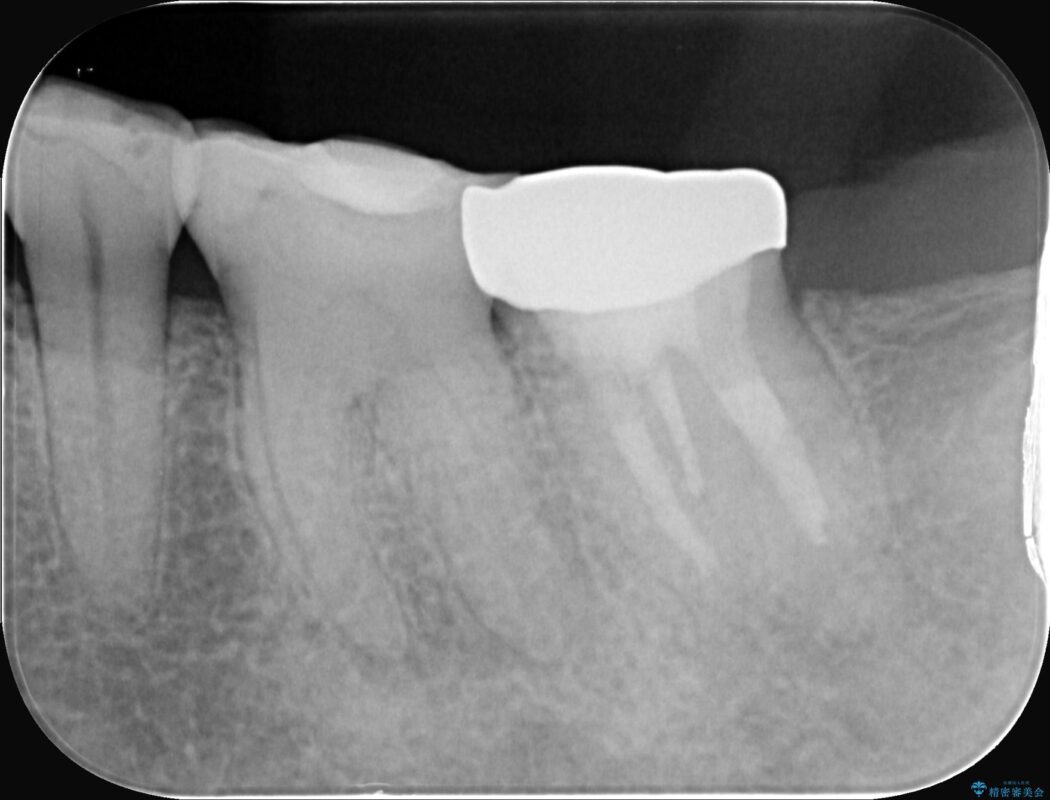

レントゲンを確認すると、歯髄腔が狭くなり根管が石灰化している難症例でした。

今回の治療は、特に難易度の高い石灰化した根管が対象でした。

まず、治療中の細菌感染を防ぐためにラバーダムを使用。次に、歯科用顕微鏡で治療部位を何十倍にも拡大しながら、狭窄した根管の入り口を探し、慎重に拡大・清掃を行いました。顕微鏡を用いることで、肉眼では不可能だった根管内部の細かい構造を確認しながら、感染源を徹底的に除去することができました。これにより、難症例の奥歯でも再発リスクを抑えた適切な処置を行うことができ、治療後に痛みは解消。大切な歯を長期間にわたり保存することができました。